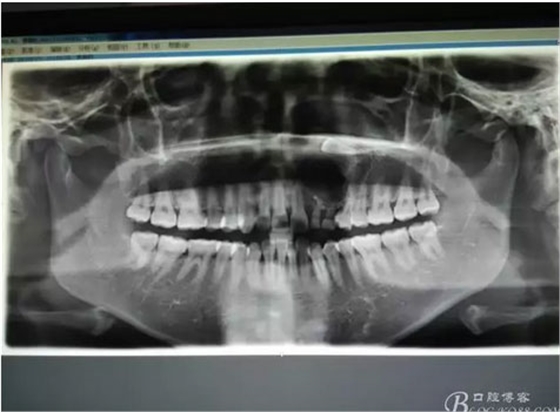

圖1。術前的CBCT影像檢查:22位于鼻底下方,23位于24、25的根方。左側(cè)乳Ⅱ、Ⅲ根方顯示囊性改變,囊腔內(nèi)大量致密鈣化團塊,密度高。

圖21.術中拍全景片,看是否有牙瘤殘留,發(fā)現(xiàn)左側(cè)乳Ⅱ根尖區(qū)還有少量致密鈣化物,建議拔除左側(cè)乳Ⅱ、,患者要求保留兩個乳牙。經(jīng)協(xié)商,遺留極少量鈣化物,不影響整體愈合。通過骨腔探查,發(fā)現(xiàn)左側(cè)乳Ⅱ、Ⅲ根尖區(qū)未破壞,骨壁尚完整。同意遺留部分鈣化物。有點缺憾,為了保留乳牙和患者的美觀及功能。定期觀察遺留部分的發(fā)展變化